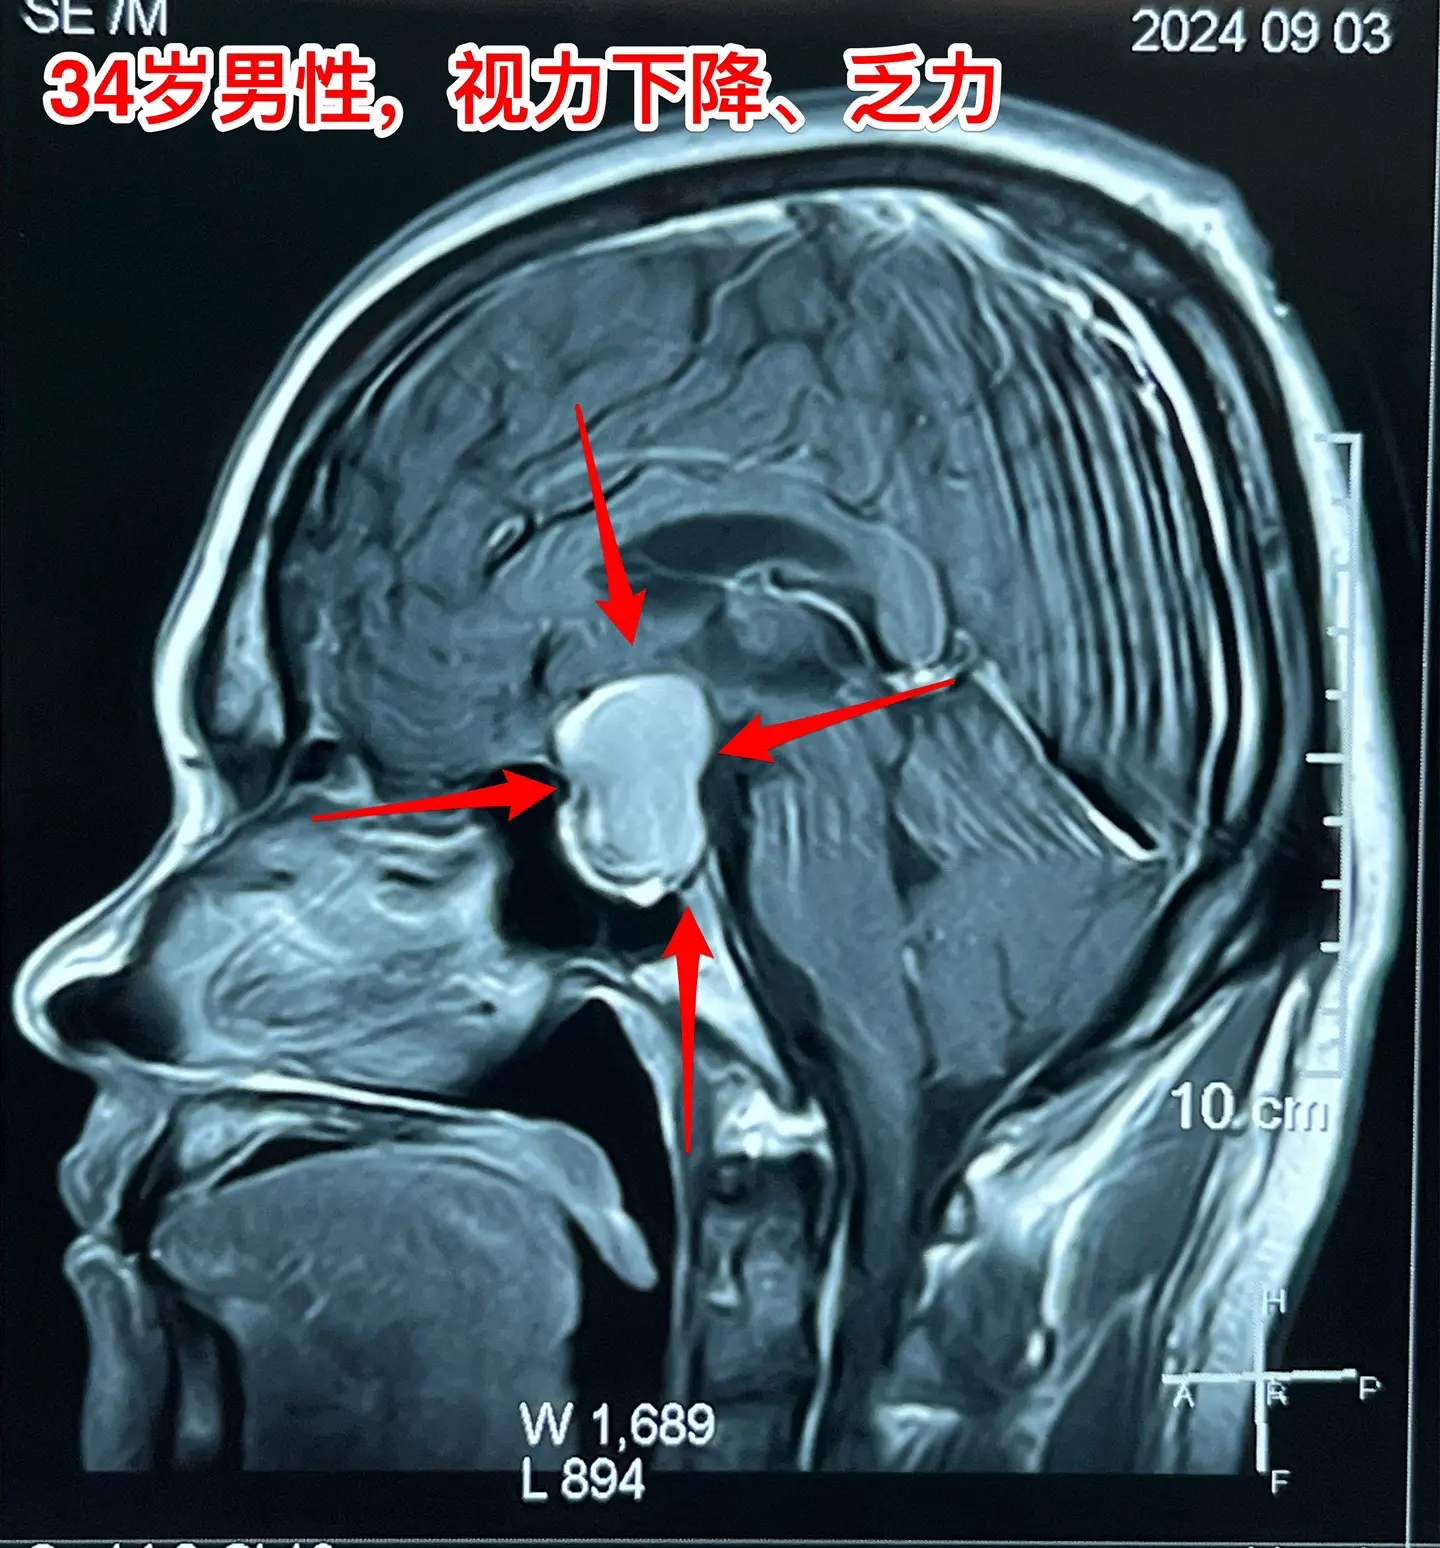

34岁男性视力下降、三个月体重下降30斤。34岁山东滕州男性,视力下降半年,头痛、恶心、乏力4个月,同时食欲不振,三个月体重下降30斤。在当地医院内分泌科住院检查,发现鞍区囊性病变,没有钙化。

这是颅咽管瘤还是拉克氏囊肿?

我们把拉克氏囊肿放在第一位。有时候这两种病还是很难鉴别的。

2024.9.2到我科住院,9月6日行开颅手术,将鞍区囊肿切除,术中见囊肿壁较薄,无钙化,囊肿得到完全切除,一部分垂体和垂体柄得以保留。

手术后患者视力明显改善,精神也好转。9月12日出院了。病理报告就是拉克氏囊肿。